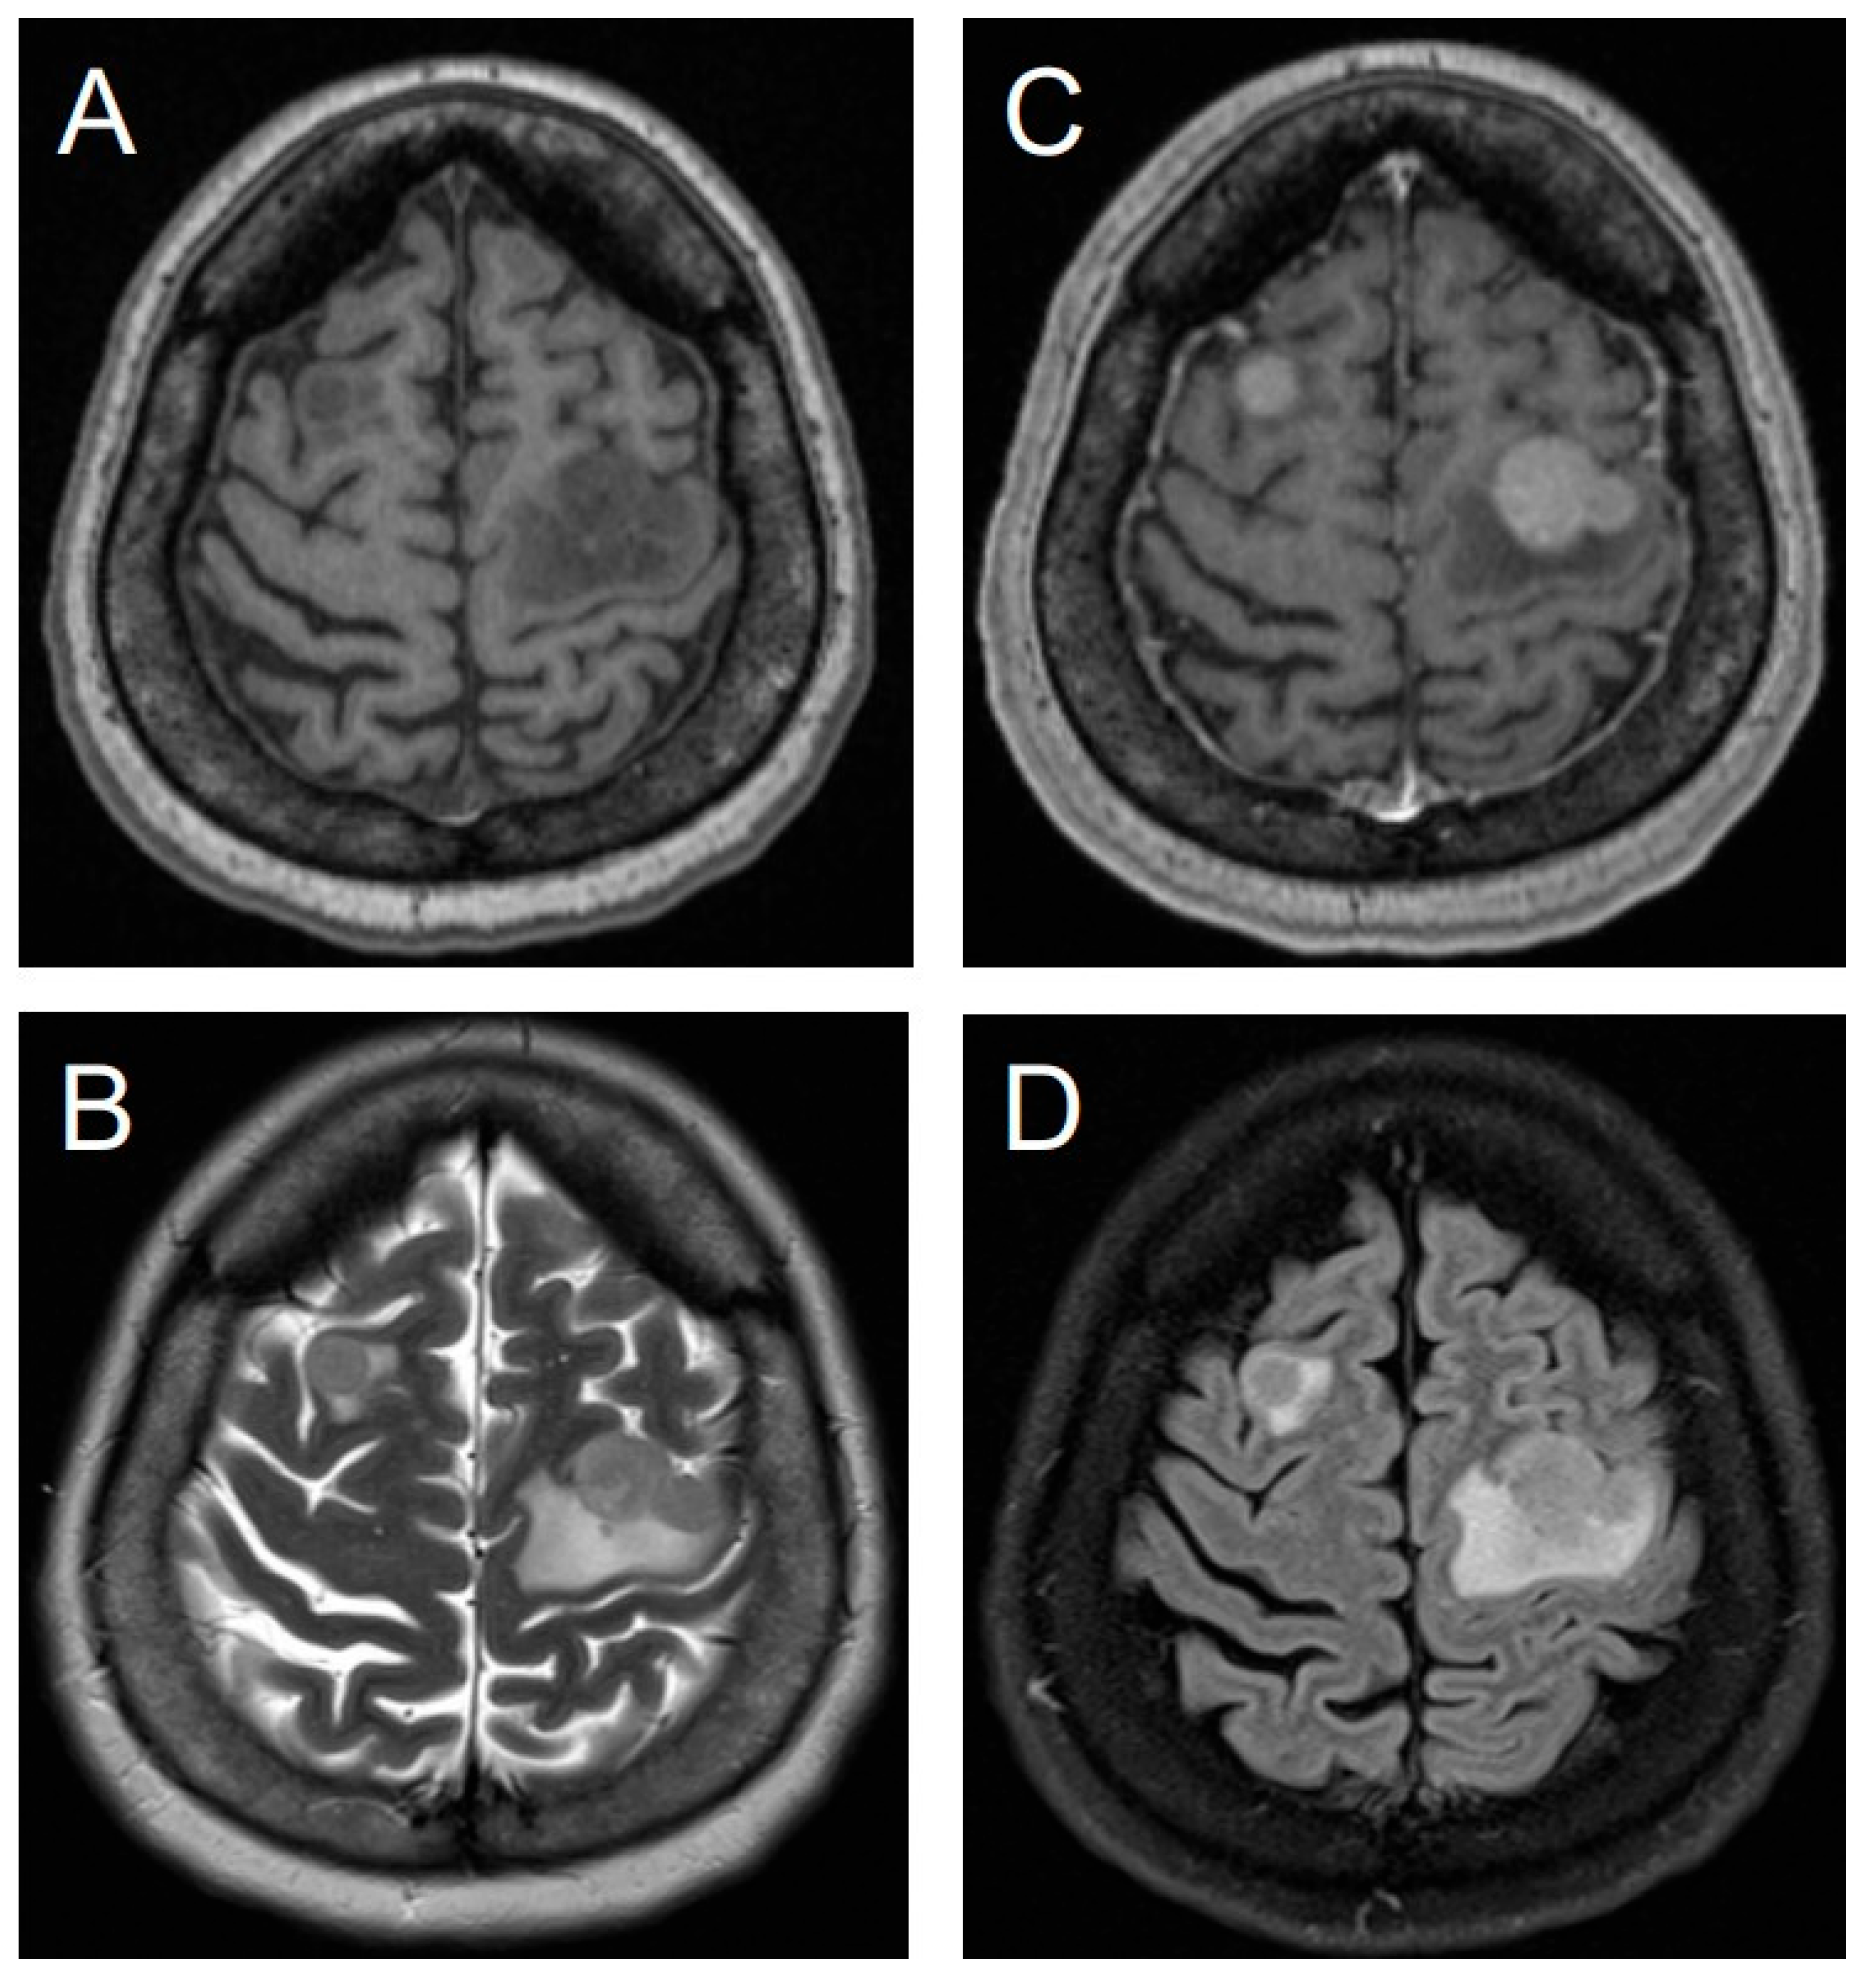

3.8. Illustrative Case